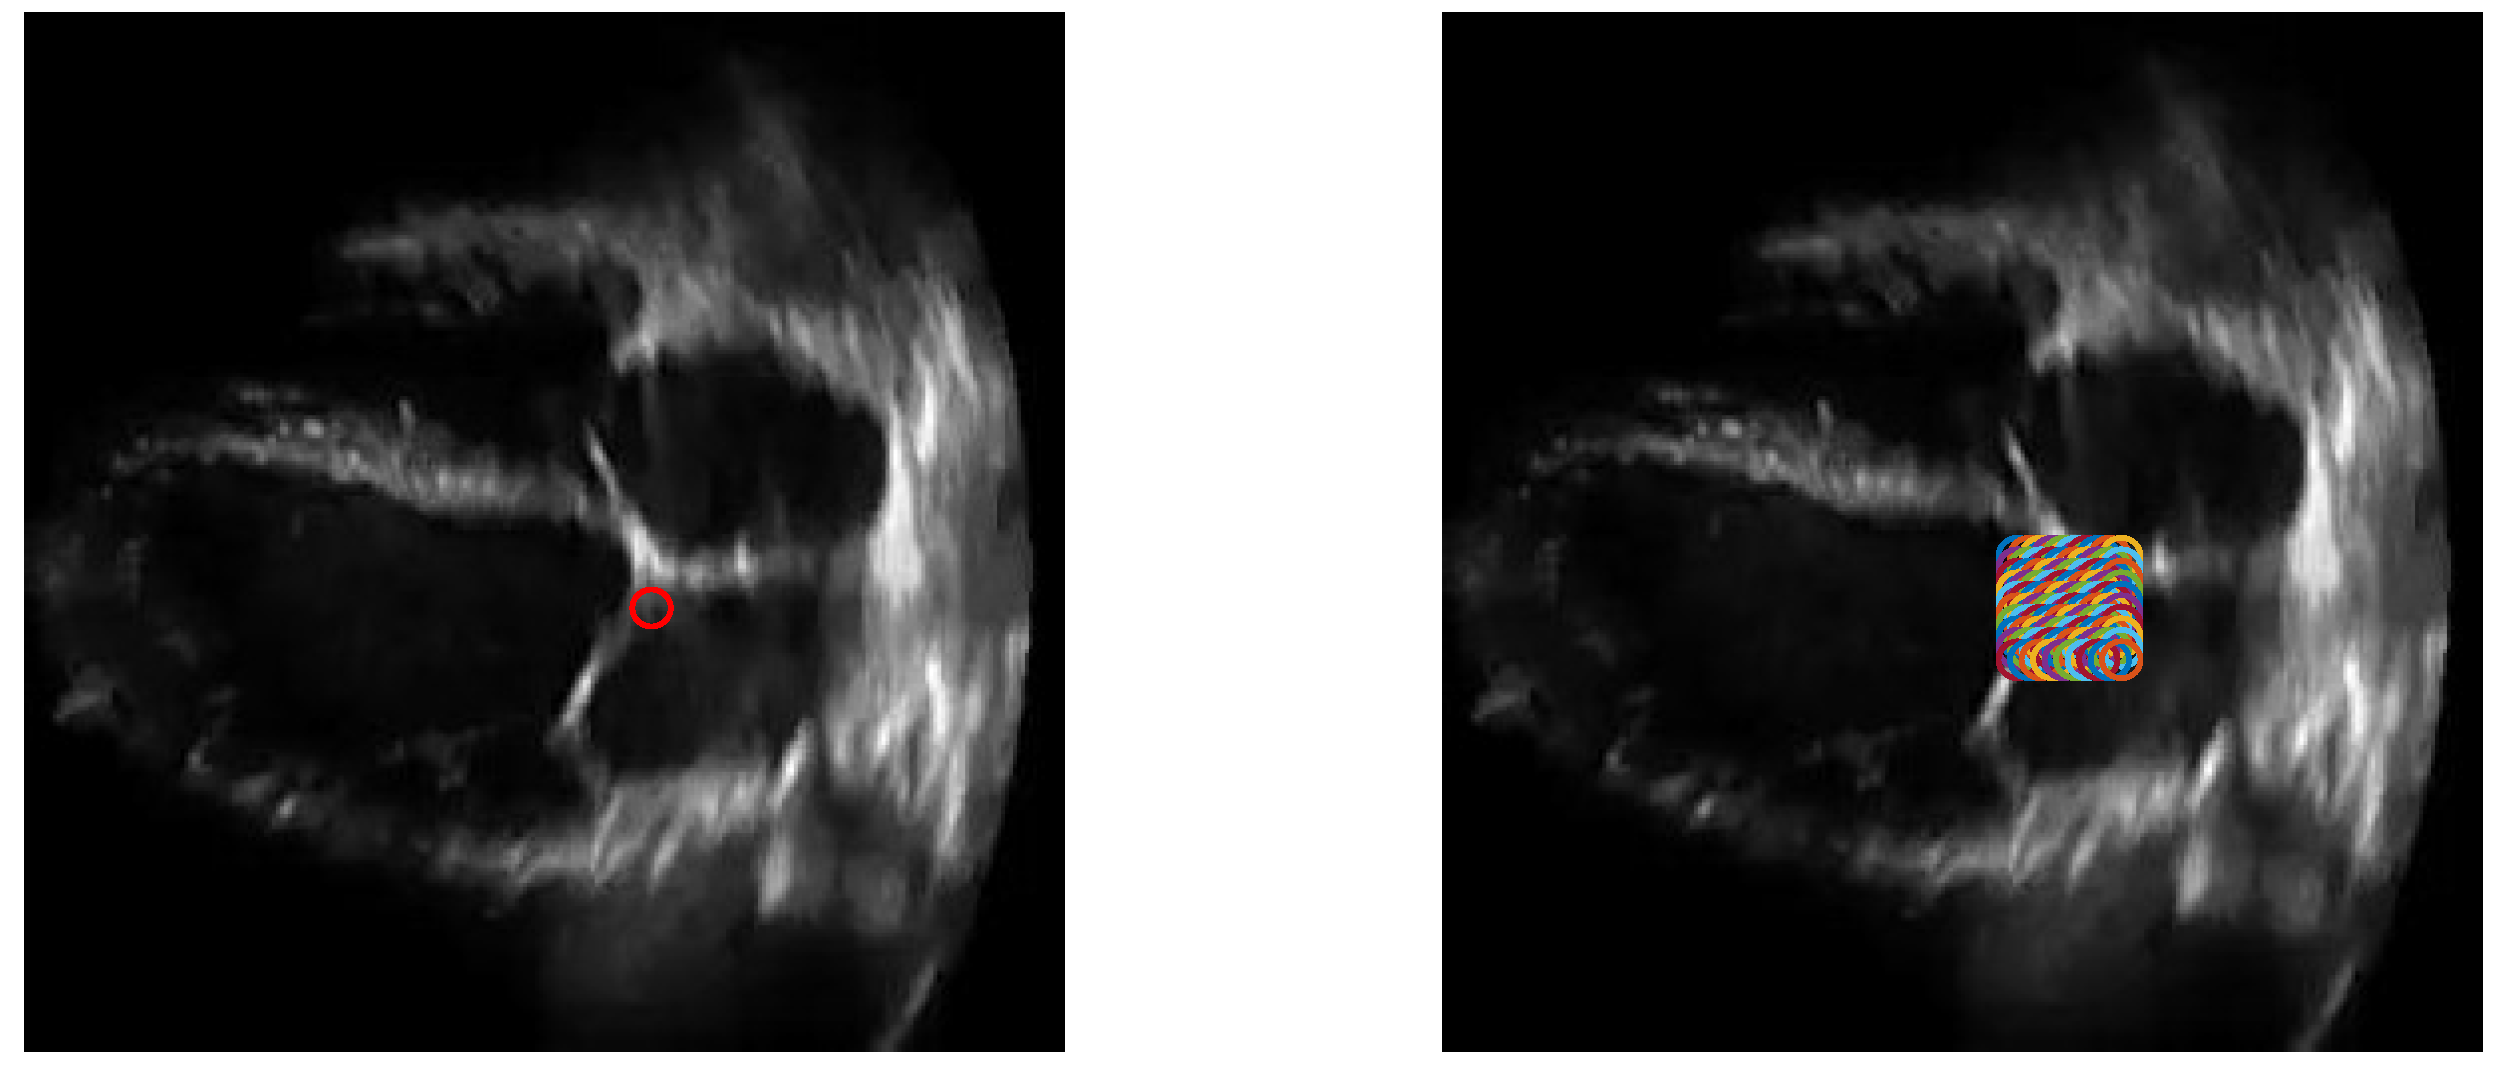

After the previous step, we take the coordinates of the remaining pixels containing 1’s and find their centroid, and measure the Euclidean distance of the centroids across different frames. This is done so that we find the two frames that exhibit the maximum range of motion shown by the mitral valve, as the two frames with the farthest centroids will correspond to the frames where the mitral valve leaflets are fully open and closed. We assume the two frames to be B S x and B S y . After finding these two frames, they are combined, along with the previously subtracted background. The final combined image is essentially B x + B y . We label this combined image as C R w × h . We consider the background subtracted version of this to be C S . Figure 1 shows three images, where (a), (b) and (c) would be B x , B y and C respectively. Please note that C allows us to observe a closed boundary around the left atrium, while even (a) is unable to do so, since the involuntary movement of the heart makes the interatrial septum to be out of the viewing plane. Reiterating, B x is the binarized version of F x , and  B S x is the binarized version of F S x . The presence of S signifies the presence of background subtraction.

Figure 1. Two frames of a heart’s ultrasound video after binarizing, (a,b) are the two frames whose centroids are farthest from each other, (c) is obtained by combining the two, i.e., B x + B y .

Figure 15. An ultrasound image with one initialization point (left) and 100 points (right).